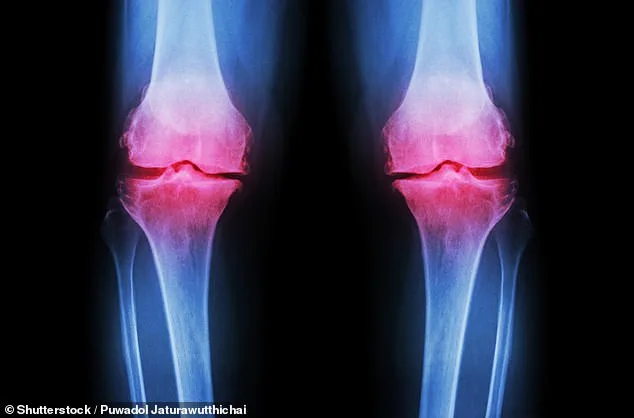

Osteoarthritis occurs when cartilage deteriorates, leading to painful and stiff joints that struggle to repair themselves. Current treatments focus heavily on pharmaceuticals, which can cause side effects like gastrointestinal distress or drowsiness, or on extensive physiotherapy regimens many find difficult to maintain long-term. The study challenges this paradigm by exploring a simple dietary intervention: adding inulin to one's daily routine. This prebiotic fibre feeds beneficial gut bacteria, triggering the production of anti-inflammatory short-chain fatty acids like butyrate, which may reduce systemic inflammation and ease pain perception.